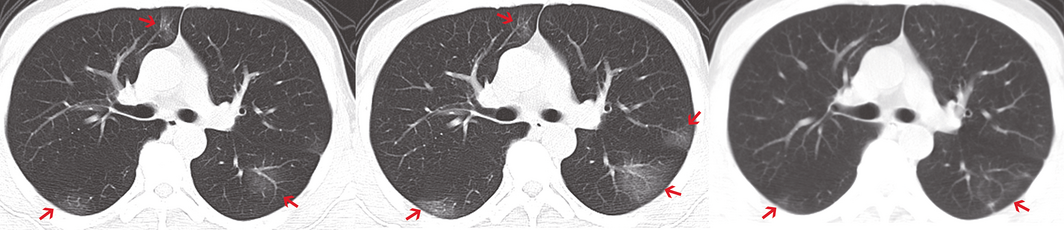

For 29 of the 31 patients, pneumonia was evident on chest CT imaging, including 20 with bilateral involvement (Supporting Information); for two patients, no abnormalities were evident on chest CT at any point. The typical radiological changes were bilateral or bilobular ground glass opacity that usually progressed within one week (Box 2).

Box 2 – Chest computed tomography (CT): typical findings, including bilateral involvement and ground glass opacities (arrows) that resolved within one week